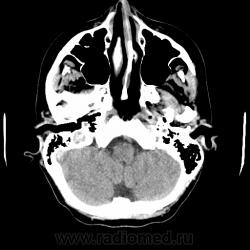

Прислали проконсультировать девушку, диагноз при направлении - САК? 32 года.

У меня возникли разногласия с клиницистами. Попрошу высказать свое мнение по поводу предоставленных томограмм с диффрядом. Заранее спасибо. Ценна любая информация. История быва пустая как обычно, единственное, что разузнал - беспокоит головная боль, были эпизоды повышения температуры.

Скан указанный в сообщении. Субстрат тени на скане? (кальцинат? кровь?)

5 лет прошло, наверняка уже неактуально, но расценил бы, как вероятную сосудистую мальформацию.

Спасибо. Без контрастирования сосудистая мальформация может так выглядеть? К сожалению автор случая пока не ответил на моё сообщение.

Коллеги, не могу вспомнить. Это кровь была точно. Насколько помню, потом обнаружилась мелкая кавернома на МРТ.